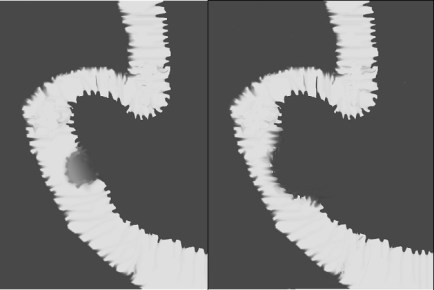

SIGNO DEL DOBLE CONDÓN

En la radiografía simple de abdomen, la presencia de bolas de narcóticos colocadas dentro de preservativos en el colon dan una apariencia de anillos muy típicos. En este ingenioso sistema de transporte, la bola de narcótico es envuelta por dos preservativos, cada uno de los cuales está plegado tres veces sobre sí mismo. El aire atrapado entre cada una de las capas de los preservativos produce una imagen radiolúcida patognomónica.

No tenemos ninguna imagen de este signo, ya que en nuestro medio las bolas de hachís no se introducen en preservativos, sino en bolsitas de plástico, que sí se ven en la imagen superior.